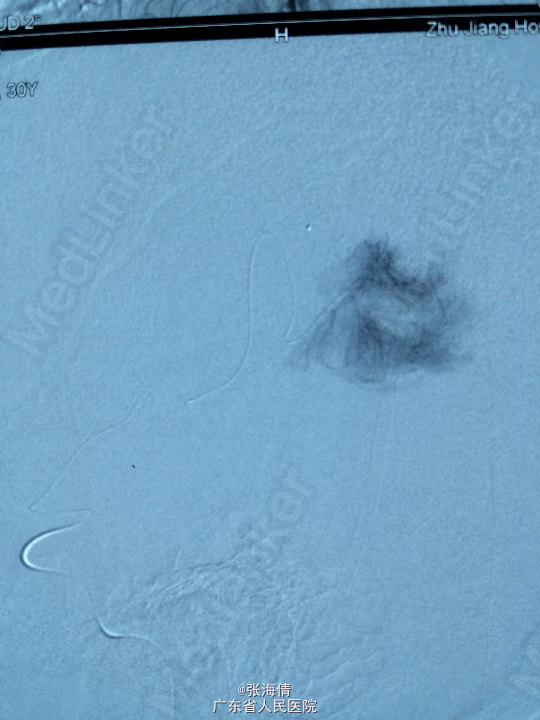

诊断:脑膜瘤 处理:先予DSA以明确肿瘤供血情况,术中脑膜瘤供血丰富,用PVA颗粒超选到供血动脉将其闭塞。后再择期在气管全麻下行脑膜瘤切除术。